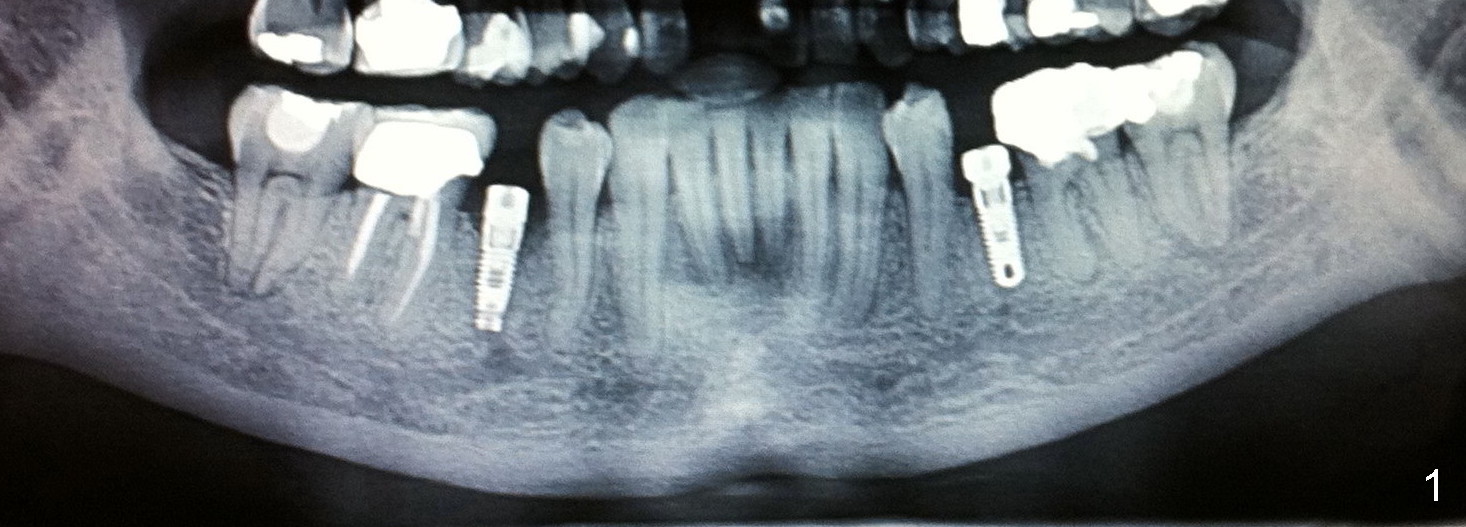

Fig.1 shows two implants placed at the sites of the lower 2nd premolars after multiple surgical procedures: extraction, soft and hard tissue graft. The patient experiences lower right lip paresthesia immediately post implantation and tenderness over the mental foramen 6 months postop. In my opinion, the depth and position of implant is difficult to control once the socket heals unless CT is taken every step of osteotomy. Fig.2 illustrates why and how immediate implant should be placed in anatomically challenging areas.